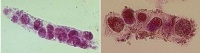

כדוריות דם אדומות בשתן יכולות להופיע בבחינה מיקרוסקופית בצורתם האופיינית, או תפוחות בשתן מהול (למעשה בצורת צלליות תאים-ghosts), או כתאי דם משוננים (crenated) בדגימות שתן מרוכזות. קשה לעתים להבדיל בין אריתרוציטים תפוחים, המוליטיים למחצה, או משוננים לבין לויקוציטים בשתן. כמו כן צלליות של אריתרוציטים עלולים להראות כפטריות. הופעה של אריתרוציטים דיסמורפיים בשתן מרמזת למחלה גלומרולארית כגון גלומרולו-נפריטיס, באופן שכדוריות אדומות הנדחסות דרך מבנים גלומרולאריים לא נורמאליים, עלולות לקבל צורה מעוותת. הנזק לצורת הכדורית יתגבר גם כתוצאה מנזק אוסמוטי שנגרם להם באבוביות הכליה. כדוריות אדומות מעוותות אלה מכונות "תאי G1" עם צורת כעך ובליטת דמויות אוזניים בצידן.

בדרך כלל נגלה casts בקצב זרימה איטי של השתן, בריכוזי מלח גבוהים, וב-pH נמוך. כאשר בכל אלה נגרמת דה-נטורציה של חלבונים ושקיעתם. רבדי hyaline ניתן למצוא בדגימות שתן של אנשים בריאים לחלוטין. תאי דם אדומים נוטים להדבק ביניהם וליצור גם כן רבדי אריתרוציטים, המעידים בדרך כלל על גלומרולו-נפריטיס עם דליפה של אריתרוציטים מפקעיות הכליה, או שהם יכולים להעיד על נזק טובולארי חמור.

רבדים של לויקוציטים אופייניים למצב של pyelonephritis חריף, אך הם יכולים להופיע גם בגלומרולו-נפריטיס. נוכחותם מעידה על דלקת כליה שכן רבדים אלה לא יווצרו בשום אתר אחר בדרכי השתן פרט לכליה. כאשר רבדים תאיים נותרים בנפרון זמן מה לפני שהם נשטפים לשלפוחית השתן, התאים יכולים להתנוון וליצור רובד גרנולארי גס, שיכול גם להופיע בצורת ובד שעווה (waxy cast). רבדים גרנולארים ושעוותיים מקורם מתאים טובולארים. הם בדרך כלל מופיעים מאבוביות ניזוקות ומשקפים לעתים קרובות מצב של ESRD.